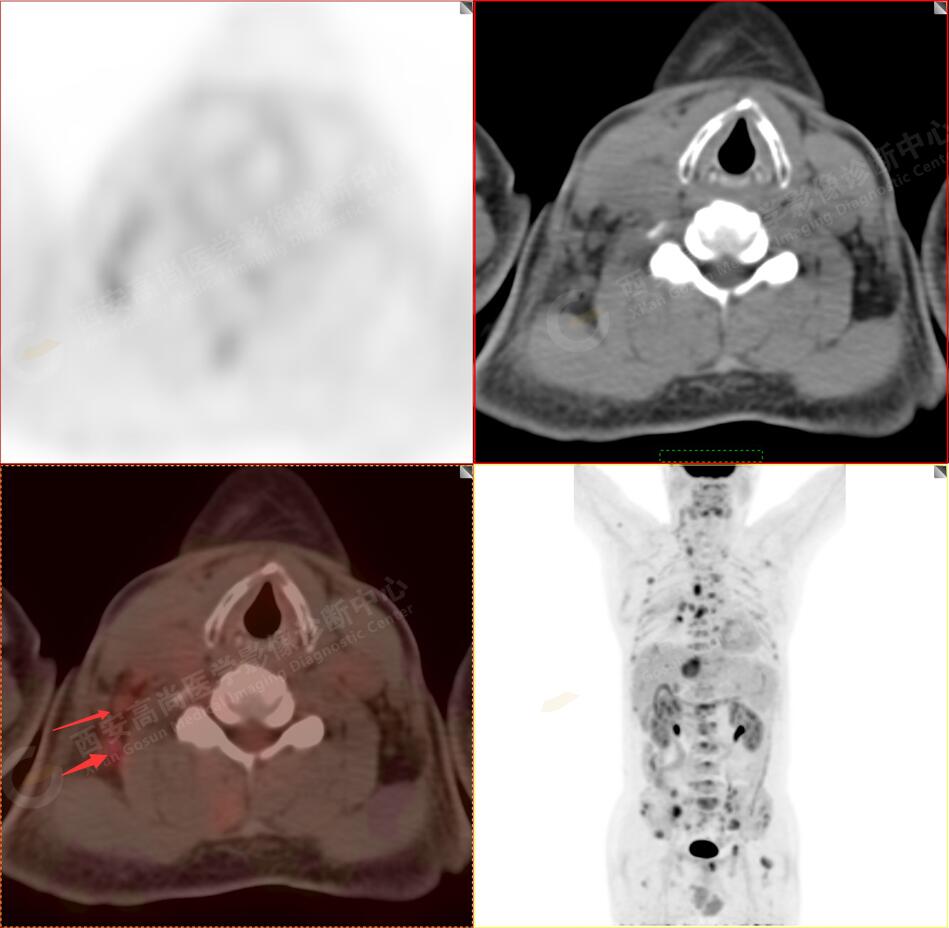

2.以下為全身多發(fā)轉移灶

3.右側頸部(Ⅱ-Ⅴ區(qū))、右側腋窩區(qū)、右側肺門及縱隔(1R、1L、2、4、6、7組)、肝門區(qū)多發(fā)腫大淋巴結,呈不同程度異常增高,均考慮為淋巴結轉移。

5.右側肱骨上段、左側肩胛骨、右側鎖骨胸骨端、胸骨、雙側多發(fā)肋骨、脊柱多發(fā)椎體及附件、雙側髂骨、雙側髖臼、雙側恥骨、雙側肱骨上段多發(fā)成骨性病變,呈不同程度FDG代謝異常增高,考慮為多發(fā)骨轉移瘤。